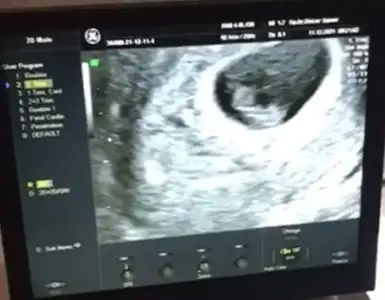

İnşallah bir mucize olur, olmazsa da şükür ki çocukların var eminim bir cesaret daha gelir.Kızlar ben bugün yine doktora gittim, çok kanamam olunca pazartesi kontrol, düşük de yapabilirsin demişlerdi, bebek düşmemiş ancak hala kalp atışları da tam anlamıyla oluşmamış, sadece titreşim halinde gibi görünüyor, şimdiye kadar olusmaliydi, bebek de çok büyümemisYine de şu anda kesin bişey söyleyemem dedi Dr ama ben olumsuz sonuçlanacağını düşünüyorum, yüzde 20 olumlu yüzde 80 olumsuz dedi doktor da. Perşembe tekrar doktora gideceğim, Allahım hayırlı olanı kolaylaştırsin, nasip etmeyeceğinin peşine düşürmesin inşallah. Çok şükür 2 oğlum var, son günlerde aşırı yıprandım daha da gebeliğe cesaret edebileceğimi sanmıyorum, Allah yavrularima hayırlı uzun ömür versin. Sizlere de gonullerinizdekini hayırlısıyla yaşatsın inşallah

Bende bir an şok geçirdim ne ara o kadar zaman geçti diyeYok öncekiBu da elips, kız diyorum ben de